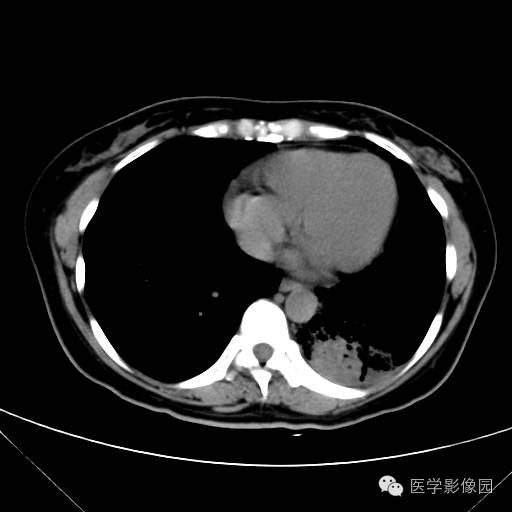

肺叶实变性支气管肺泡癌1例CT影像表现